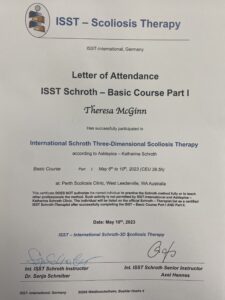

Theresa McGinn travelled to Australia in 2023 to complete the ISST Schroth course for the treatment of Scoliosis.